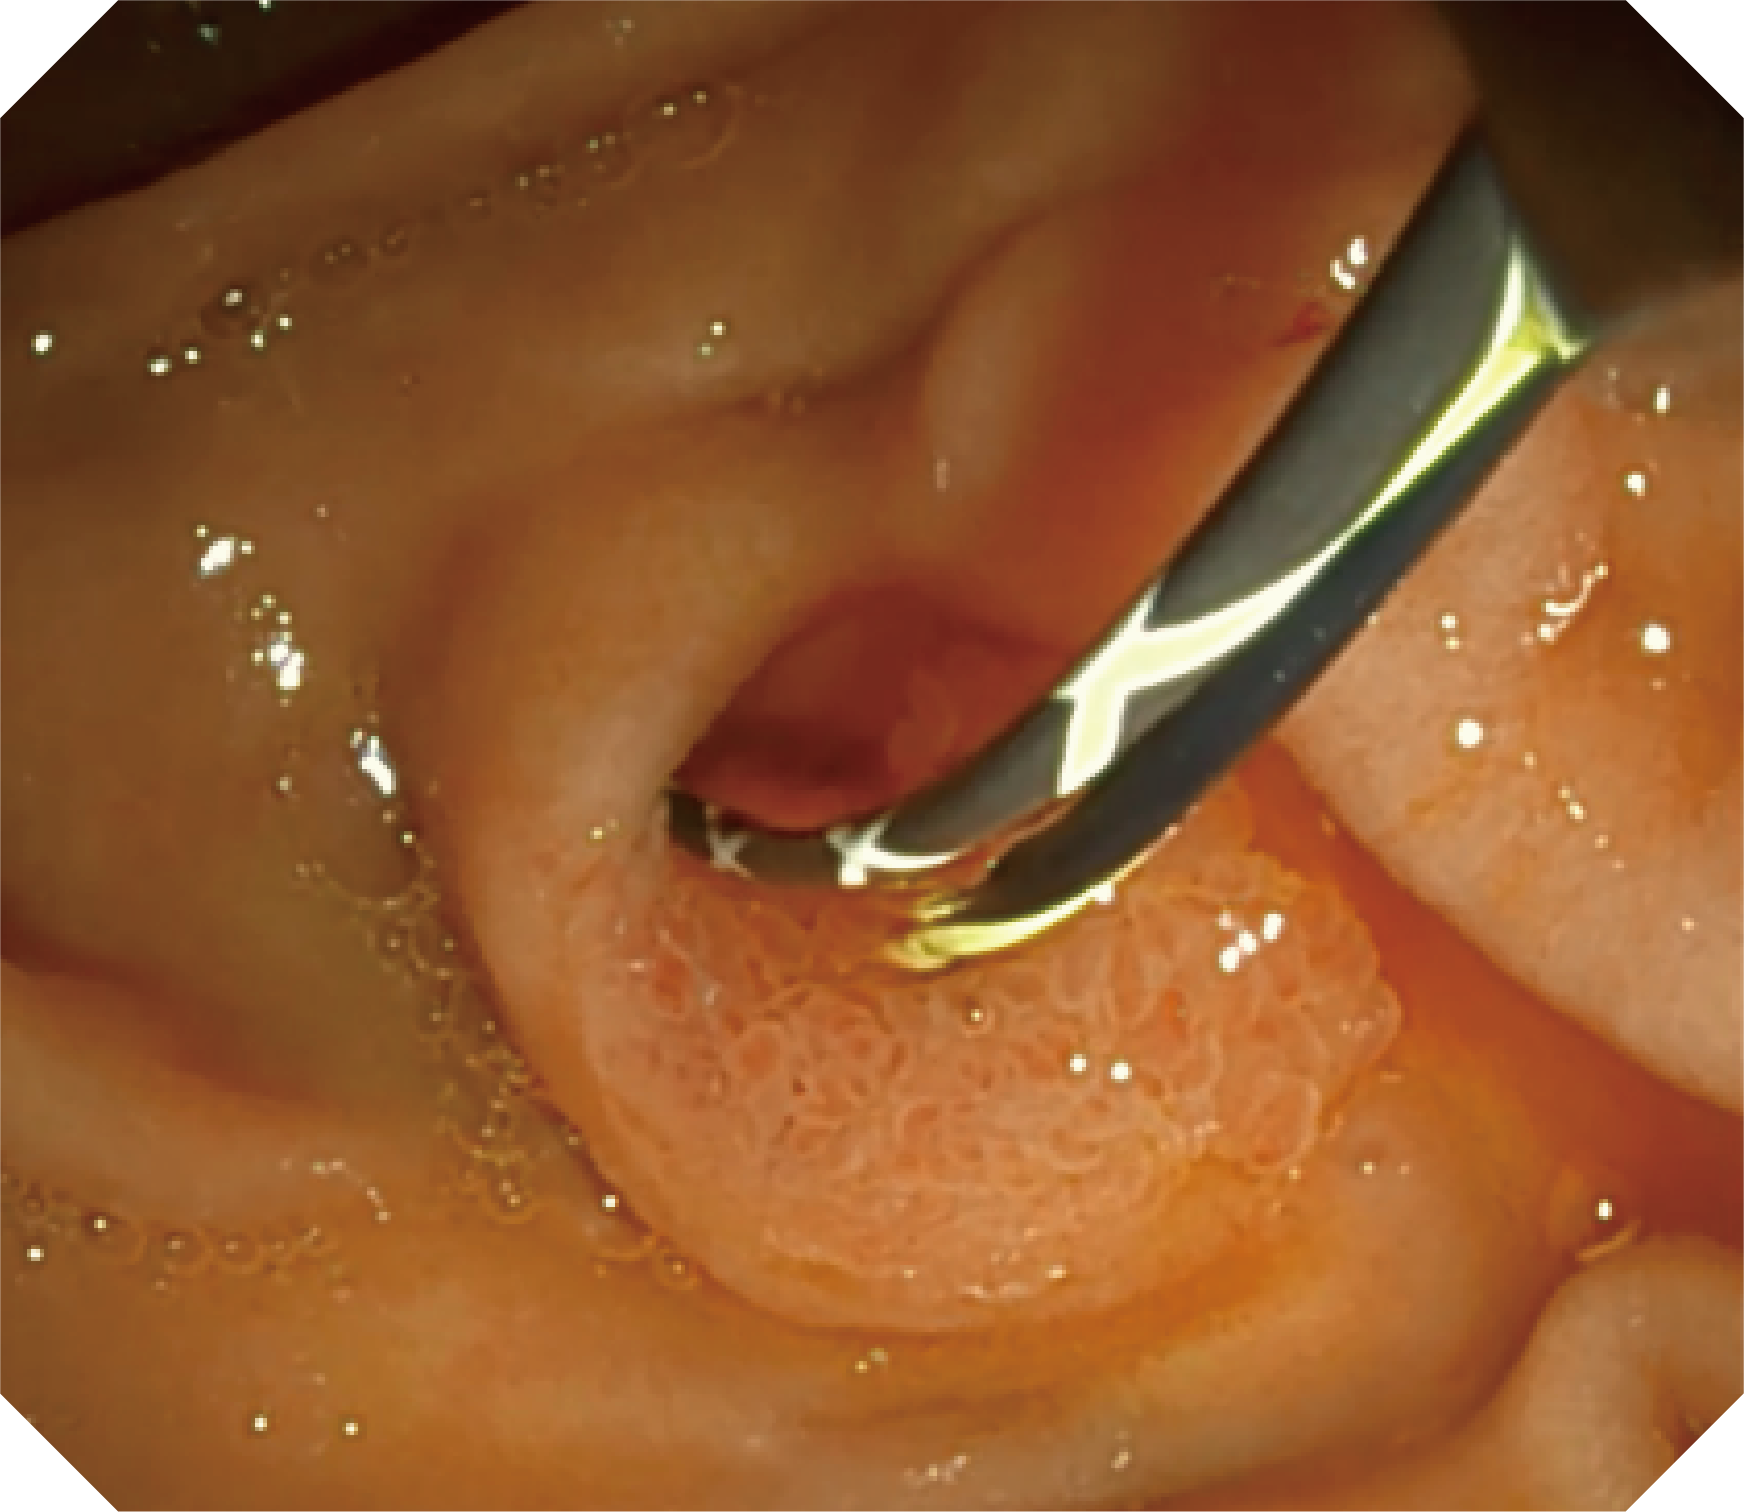

CMOS传感器提供高清内镜视野 SFI/VIST光学染色技术凸显病变区域

可拆卸先端帽

提供独立抬钳器清洗装置